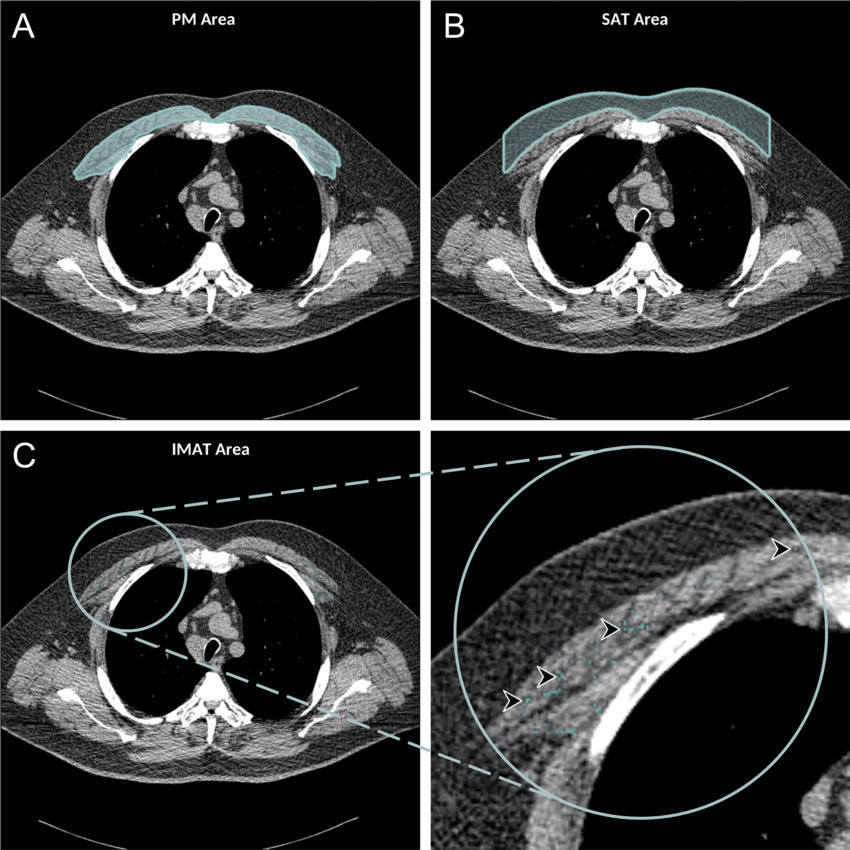

Figure 3. Axial chest CT examination in a 54-year-old participant. A, On the axial noncontrast chest CT image, the pectoralis muscle (PM) area was segmented and measured in the section above the aortic arch. B, The subcutaneous adipose tissue (SAT) area as the area between the PM and the skin surface on the same section was also measured and the attenuation of pixels in the SAT area was used to determine the individualized threshold for the intermuscular adipose tissue (IMAT). C, The IMAT within the PM was segmented as the areas with Hounsfield units below this threshold for the IMAT (arrowheads).

High-res (TIF) version